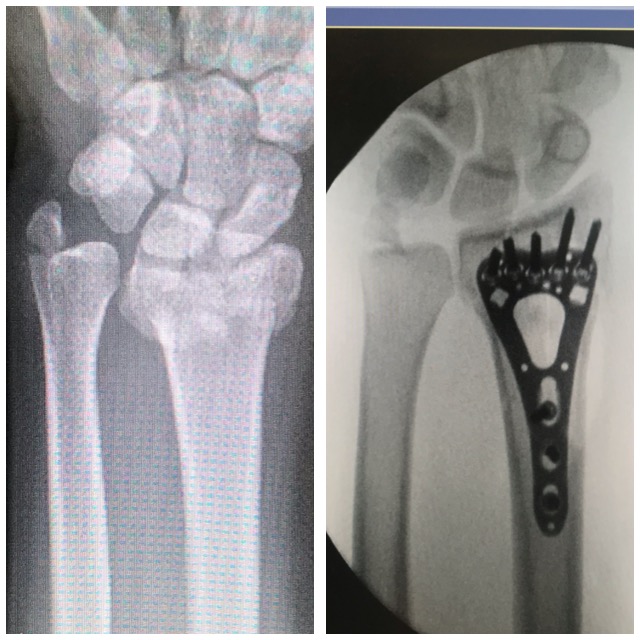

Rannemurtuma

Ennen – jälkeen